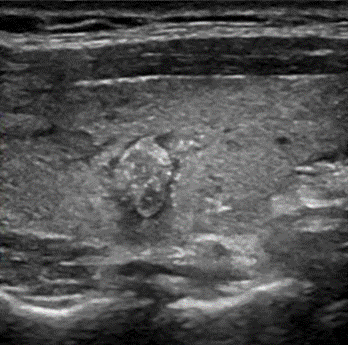

Исследование показало, что при работе со стандартными протоколами УЗИ значение «индекса согласия» между оценкой анкетируемых врачей и патоморфологическими диагнозами было велико (табл. 2). Это указывало на качественные компетенции специалистов. «Конфликт решения», когда эндокринологи и хирурги не смогли поставить по протоколу УЗИ предварительный диагноз, был лишь в 2 случаях (по 1 клиническому случаю сразу 4 врача (эндокринологи и хирурги) не смогли дать аргументированный ответ). Но один из вариантов теста УЗИ (папиллярный рак) не только был всеми врачами правильно диагностирован (рис. 1), но и при аргументации ответа получил свое обозначение как «лицо шута» (определение дал специалист – хирург: «плохое лицо» – плохой диагноз»).

Рис. 1. УЗИ. Продольный скан, В-режим. Неоднородный изоэхогенный узел размером 7х9 мм с нечетким, неровным контуром, с множественными микрокальцификатами, «высота>ширины». ТИРАДС 5. Комментарий хирурга: «лицо шута - это зло». Цитологическое исследование: Bethesda 6. Морфологическое исследование операционного препарата – папиллярный рак щитовидной железы

Составлено авторами на основе полученных данных в ходе исследования.